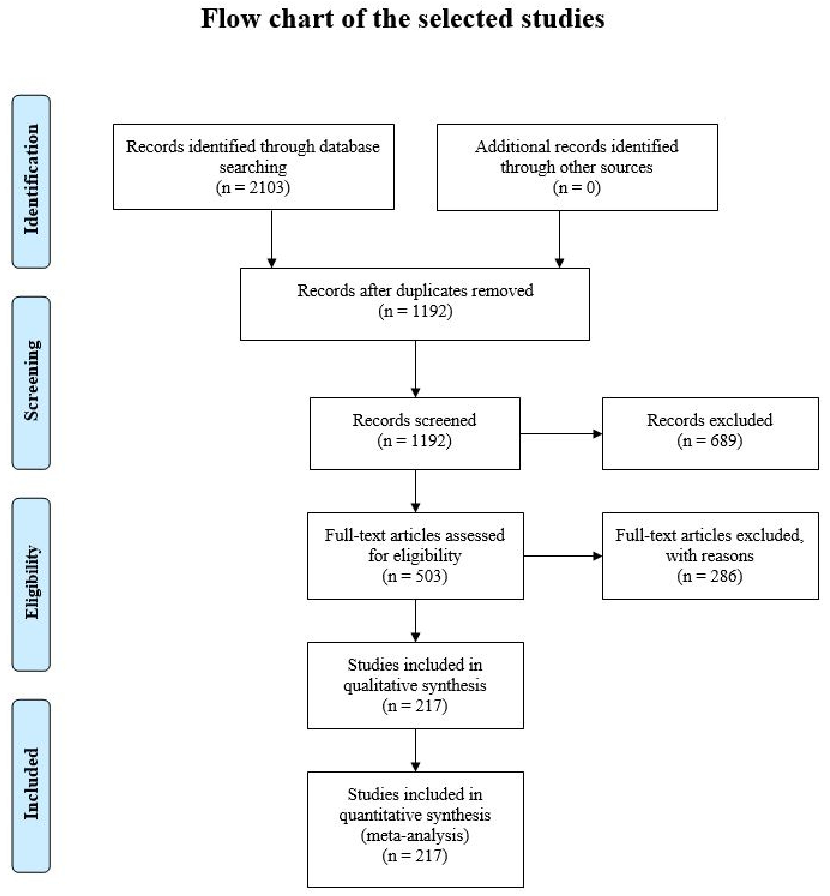

PRISMA-style flow chart shows the systematic selection process for studies included in this review on biological rhythm and chronotype in health.

Biological Rhythm and Chronotype: New Perspectives in Health.